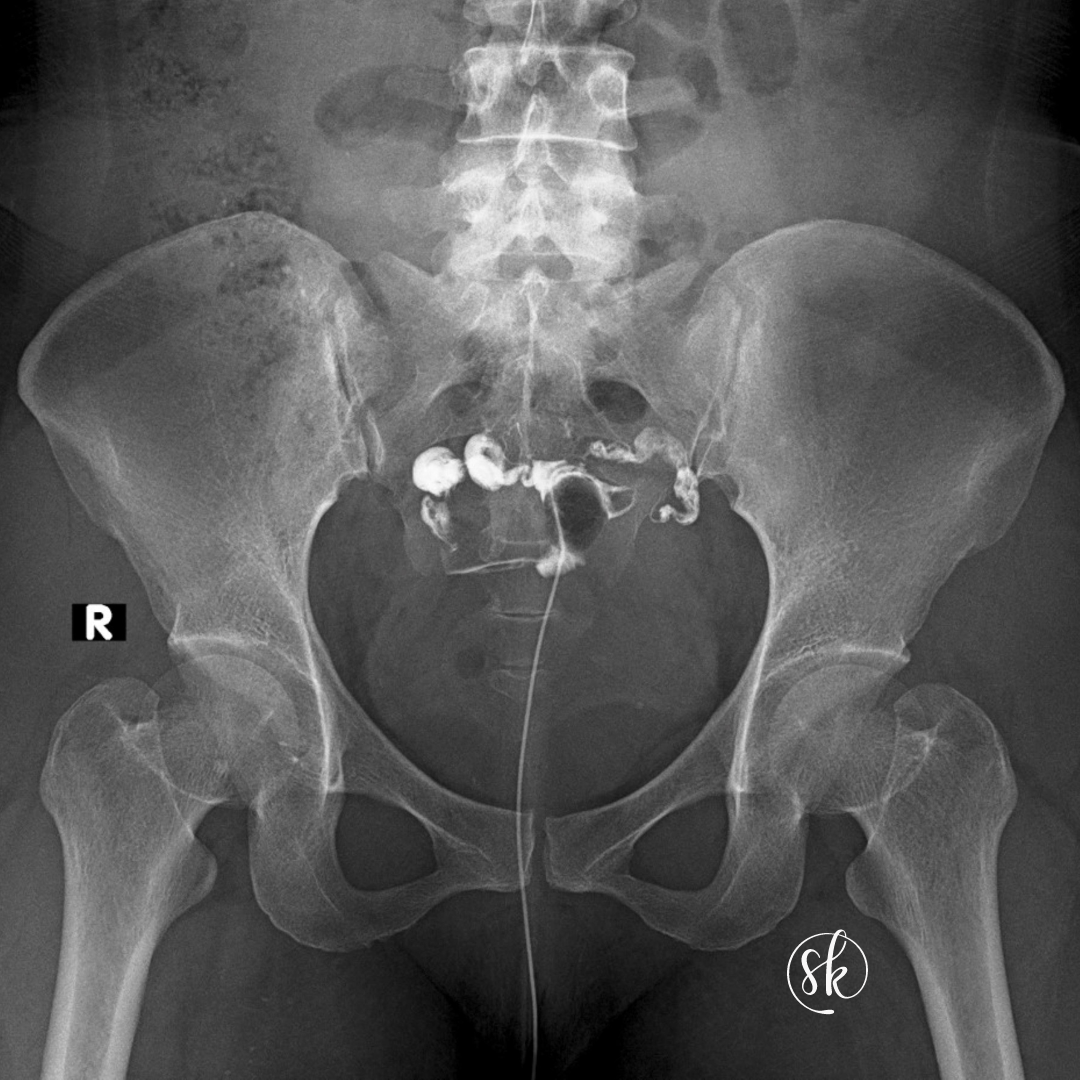

HSG

HSG adalah sama seperti HyFoSy, tetapi aliran pewarna akan dapat dilihat dengan menggunakan X-ray berbanding dengan menggunakan ultrasound untuk HyFoSy. Ia boleh menjadi agak tidak selesa sedikit tetapi kebanyakan wanita dapat melaluinya dengan baik. Terdapat juga sedikit risiko jangkitan yang boleh merebak dari vagina ke pelvis. Oleh itu saringan untuk jangkitan ditawarkan sebelum prosedur atau anda akan diberikan antibiotik.